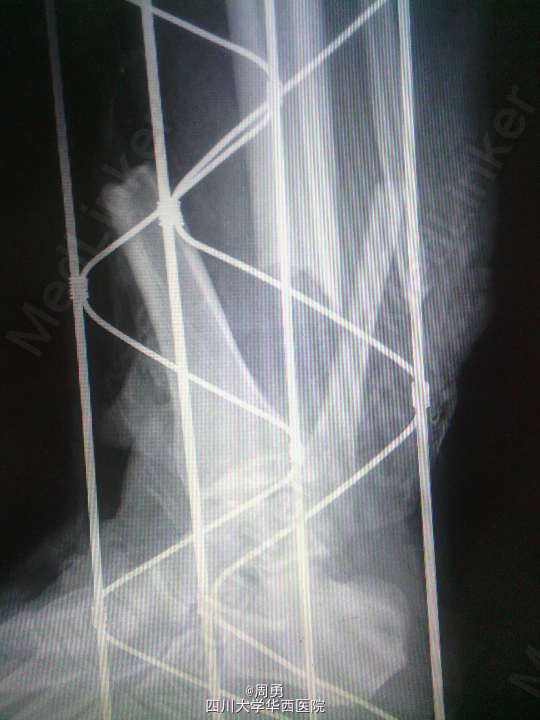

闭合穿针复位腓骨在开放性骨折中应用和意义

某些腓骨骨折常无需处理,但在开放性骨折一期处理创面同时,为了达到恢复肢体长度、条件允许情况下最大可能复位骨折、简化二期手术目的,某些时候复位腓骨并闭合穿克氏针对骨折复位和固定会有一定帮助,选几年前2个博士住院总期间X片示意,欢迎大家交流。